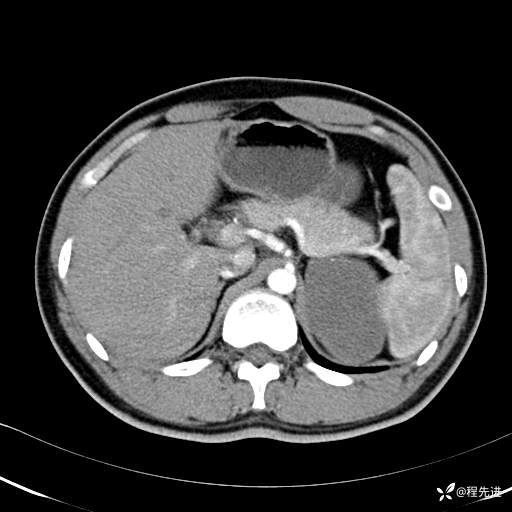

【腹盆】特别精彩病例|体检发现的左侧腹膜后占位期待您的精彩解读

患者年龄:25岁

简要病史:体检发现

CT平扫:(CT值:平扫,27HU,动脉期,27HU,门静脉期,31HU,平衡期,32HU)

CT增强:

动脉期: